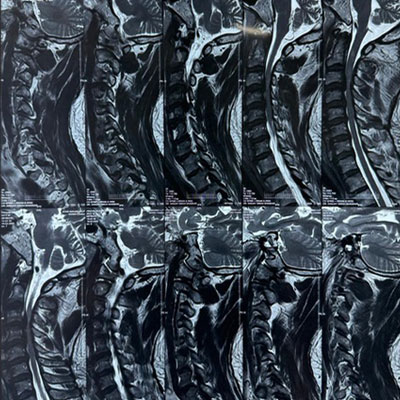

Dr. Ujwal Yeole is an experienced neurosurgeon specializes in treating a wide spectrum of neurological conditions including neuro-oncology, peripheral nerve disorders, vascular disorders, spinal pathologies, pediatric neurosurgery, neuro-trauma and skull base neuroendoscopic procedures.